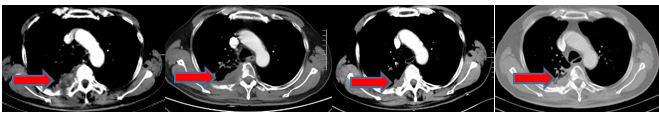

手术被认为是非小细胞肺癌(NSCLC)的主要治疗选择,然而只有25%~30%的患者能做根治性切除,5年生存率在从Ia期到IIIa期介于67%和23%之间,部分II...